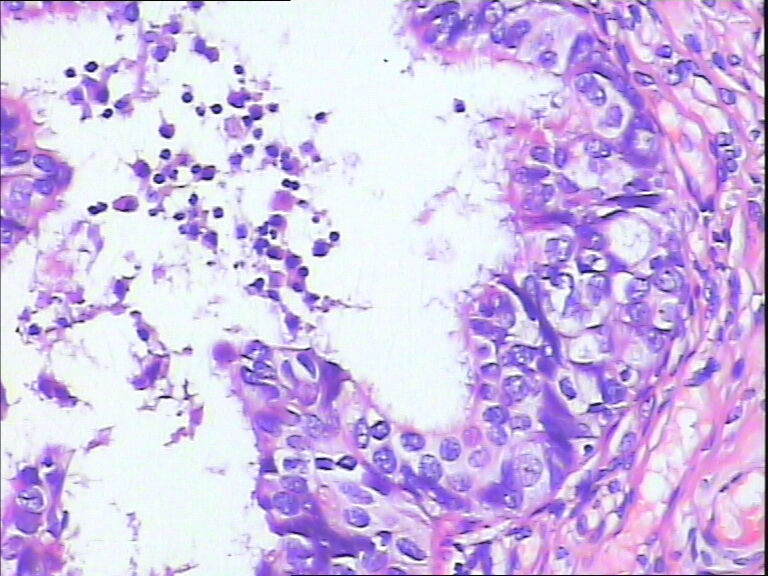

女,43y

左输卵管积液

输卵管长4.5cm;直径:0.8cm

慢性炎伴上皮增生

输卵管增生性上皮病变。

良性,炎症改变

考虑炎症